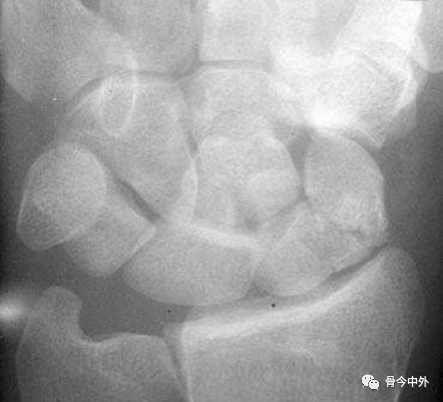

图2 成人期腕关节正侧位及舟骨蝶位片。1.舟骨;2.月骨;3.三角骨;4.豆状骨;5.大多角骨;6.小多角骨;7.头状骨;8.钩骨;9.桡骨茎突;10.尺骨茎突;11.第一掌骨基部。